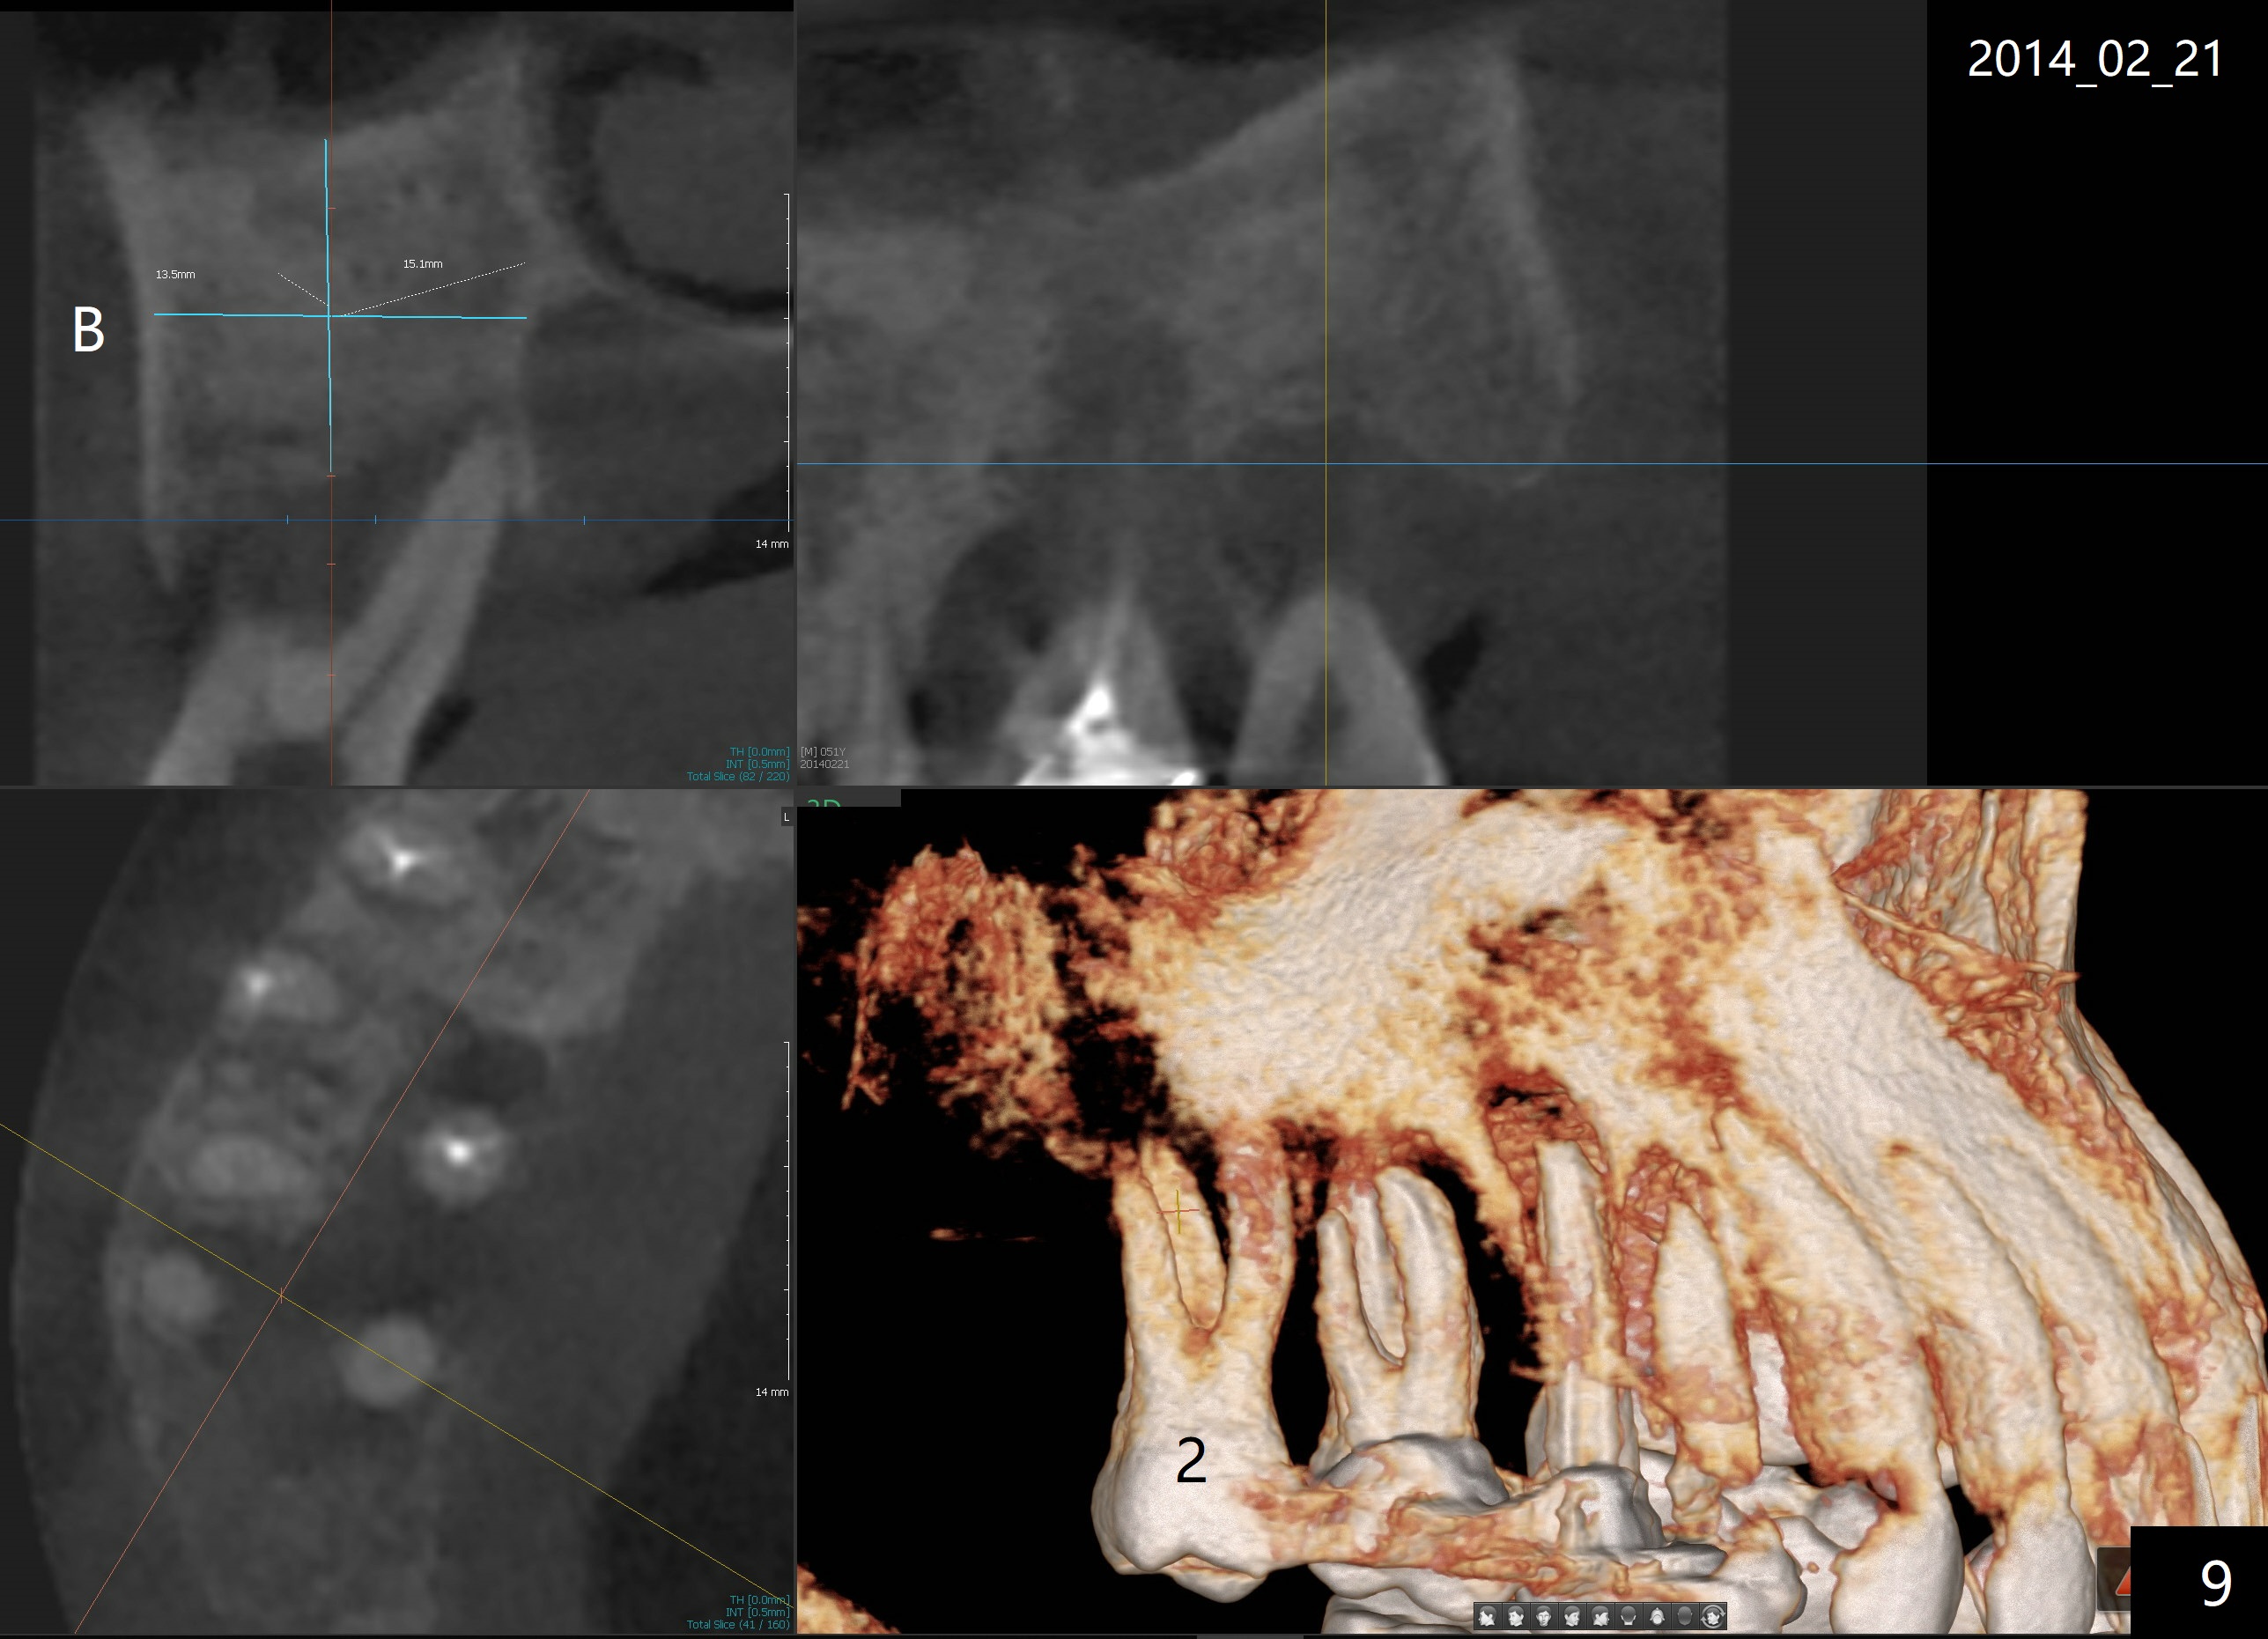

It appears that the upper molar shifting is quite common (6 7), probably due to less dense bone in the maxilla. It is the best to fabricate and keep an immediate provisional to hold the mesiodistal dimension and ask the patient to improve local oral hygiene during osteointegration. The implant crown is functioning 4 years 2 months post cementation while there is severe bone loss at #2 (Fig.8). An immediate implant could be placed at #2 (Fig.9), while a wide delayed implant will be placed at #31 (Fig.10).

2